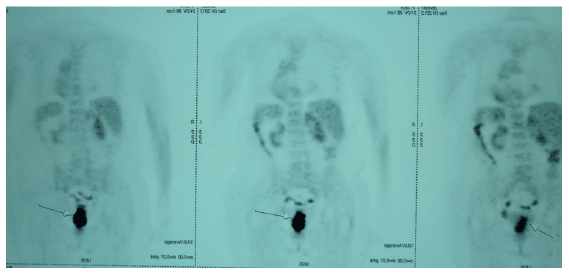

为患者设计了一个MSCT方案,包括奥沙利铂、5-氟尿嘧啶(5-FU)和亚叶酸钙(FOLFOX6)的组合,在应用药物剂量的胰岛素后给药。在患者书面知情同意的情况下,该方案每周交付一次,为期3个月。胰岛素输送和化疗输注始终与血糖监测同时进行。与MSCT相伴;患者还接受了外照射治疗,总剂量为50.6 Gy,分22组,每周5天,为期一个月。在MSCT期间,患者在每次化疗后每周接受一次局部HT。Oncotherm(Troisdorf,德国)EHY-3010热疗装置用于热刺激,该装置使用电磁能并产生载波频率为13.56 MHz的调制电场,由两个有源电极产生并通过患者身体。在整个热疗过程中,当一个30x40 cm的移动电极放置在盆腔结肠区域时,第二个固定反电极保持在患者下方的固定位置。根据美国腹膜表面恶性肿瘤学会确定的共识指南,每次热疗持续60分钟[10]。同样根据共识指南,通过将电极的功率从80 W(瓦特)逐渐增加到130 W[8],加热到44 C。在12次MSCT和HT以及22次RT后,患者接受了第二次PET-CT(图3)。PET-CT评估显示疾病反应,直肠原发肿瘤显示后退。而肿瘤最初跨越5.5厘米的直肠段,有一辆SUV德赢vwin首页网址马克斯27.2例中,第二例PET-CT报告显示直肠壁3厘米段和一辆SUV马克斯第二次PET-CT评估后,患者继续接受相同的代谢支持化疗方案,然后进行60分钟局部热疗,为期6个月。6个月后的PET-CT评估显示,FDG摄取不一致恶性肿瘤。患者被转诊进行低位前切除,但患者再次拒绝。患者最终无病PET-CT检查后27个月,仍无病理改变。常规随访检查,CEA和CA 19-9筛查以及每3个月进行一次腹部CT评估,均未发现复发迹象.

图2:全身(18F)-氟脱氧葡萄糖(FDG)-PET-CT显示肿物,覆盖直肠5.5 cm段,伴直肠壁增厚。

图3:随访PET-CT显示原发肿瘤收缩,直肠壁增厚减少。